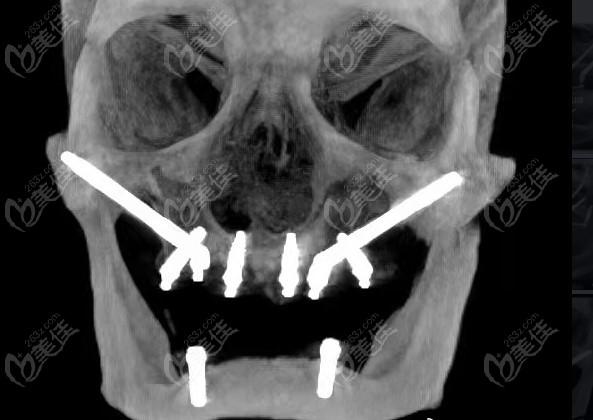

我们来了解一下穿翼种植牙到底是什么。这项技术是一种通过植入人工牙根来恢复缺失牙齿的方法。与传统的矫正牙齿相比,穿翼种植牙更为快速、方便,而且效果更加自然。它不仅可以解决单颗牙齿缺失的问题,还可以修复整口牙齿,重塑迷人的笑容。